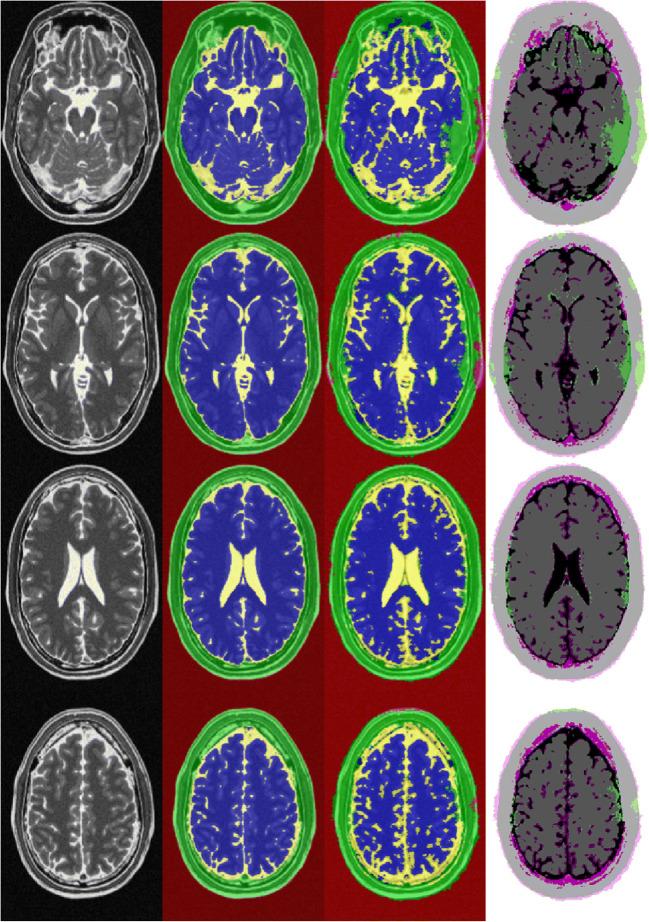

Ninety-five routinely performed true FISP MRI sequences were retrospectively analyzed in 43 patients with pediatric hydrocephalus. Using a freely available and clinically established segmentation algorithm based on a hidden Markov random field model, four classes of segmentation (brain, cerebrospinal fluid (CSF), background, and tissue) were generated. Fifty-nine randomly selected data sets (10,432 slices) were used as a training data set. Images were augmented for contrast, brightness, and random left/right and X/Y translation. A convolutional neural network (CNN) for semantic image segmentation composed of an encoder and corresponding decoder subnetwork was set up. The network was pre-initialized with layers and weights from a pre-trained VGG 16 model. Following the network was trained with the labeled image data set. A validation data set of 18 scans (3289 slices) was used to monitor the performance as the deep CNN trained. The classification results were tested on 18 randomly allocated labeled data sets (3319 slices) and on a T2-weighted BrainWeb data set with known ground truth.

The segmentation of clinical test data provided reliable results (global accuracy 0.90, Dice coefficient 0.86), while the CNN segmentation of data from the BrainWeb data set showed comparable results (global accuracy 0.89, Dice coefficient 0.84). The segmentation of the BrainWeb data set with the classical FAST algorithm produced consistent findings (global accuracy 0.90, Dice coefficient 0.87). Likewise, the area development of brain and CSF in the long-term clinical course of three patients was presented.